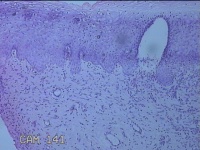

宫颈6点、12点组织

性别

女

年龄

33岁

临床诊断

人乳头瘤病毒感染

一般病史

发现HPV18,其他12种阳性近一月。

标本名称

大体所见

1.“宫颈6点组织”:灰白粉红色组织0.5x0.3x0.2cm一块。 2.“宫颈7点组织”:灰白暗红色组织0.8x0.3x0.2cm两块。

图2